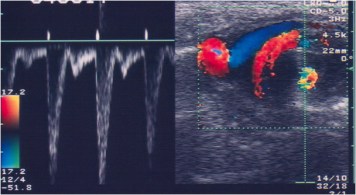

SIGNO DEL REMOLINO EN SENTIDO HORARIO

Signo de vólvulo de intestino delgado en pacientes pediátricos, en la ecografía doppler. El vólvulo provoca un plegamiento de la vena mesentérica superior y el mesenterio alrededor de la arteria mesentérica superior. En doppler se ve una imagen de remolino en el sentido de las agujas del reloj con el movimiento caudal del transductor en el plano axial.

La imagen de la izquierda muestra el espectro del doppler en el que se observa un patrón de alta velocidad. A la derecha, la imagen en modo B corresponde al arremolinamiento de los vasos mesentéricos.

Artículo de referencia: Shimanuki, Y y cols. Clockwise whirpool sign at color Doppler US: an objective and definite sign of midgut volvulus. Radiology 1996; 199: 261-264. Puedes consultar el abstract en http://pubs.rsna.org/doi/pdf/10.1148/radiology.199.1.8633156.